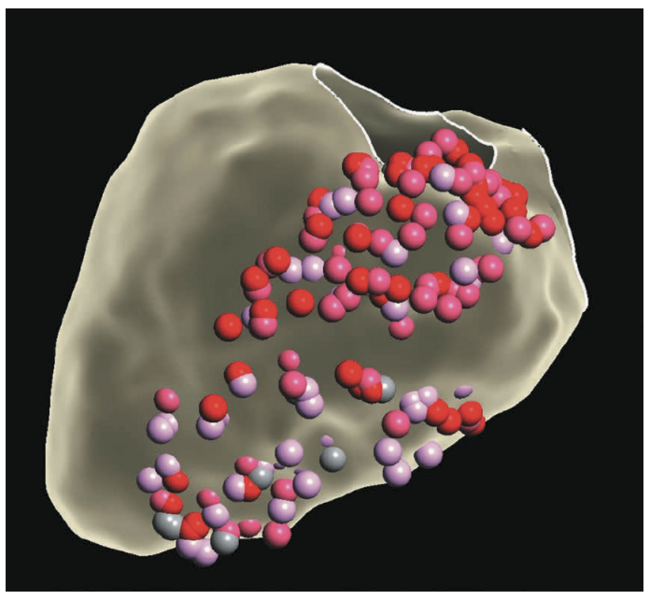

Catheter-based RF ablation remains the gold standard for the treatment of VT.10 Patients with refractory VT may fail traditional therapy due to inaccessible substrate or high-risk comorbidities precluding repeat ablation. SBRT (or stereotactic ablative radiotherapy) is a method commonly used in the treatment of solid tumors for precise delivery of radiation to tissue, with minimal interaction to adjacent tissue.11 In the first case series, Cuculich et al described use of SBRT (described as cardiac radioablation [CRA]) targeting myocardium by coupling noninvasive electroanatomic mapping with electrocardiographic imaging and multimodality imaging, including computed tomography, transthoracic echocardiography, and cardiac magnetic resonance imaging to precisely localize VT substrate in 5 high-risk patients with refractory VT.12 A dose of 25 Gy ionizing radiation in a single fraction was prescribed over the total targeted volume (Figure 6).12 Following therapy, there was a reduction from 6577 events to 4 events.11 This novel approach led to the prospective phase I/II ENCORE-VT trial demonstrating efficacy with a 97% reduction in ICD shocks and antitachycardia pacing, and improved quality of life. This therapy is thought to be easier on patients; it lasts 5-10 minutes and treatment occurs while the patient is awake, free-breathing, and listening to music. Because it is entirely noninvasive, there have been no procedural adverse events. In some centers, patients are now treated as outpatients after a 10-minute treatment.